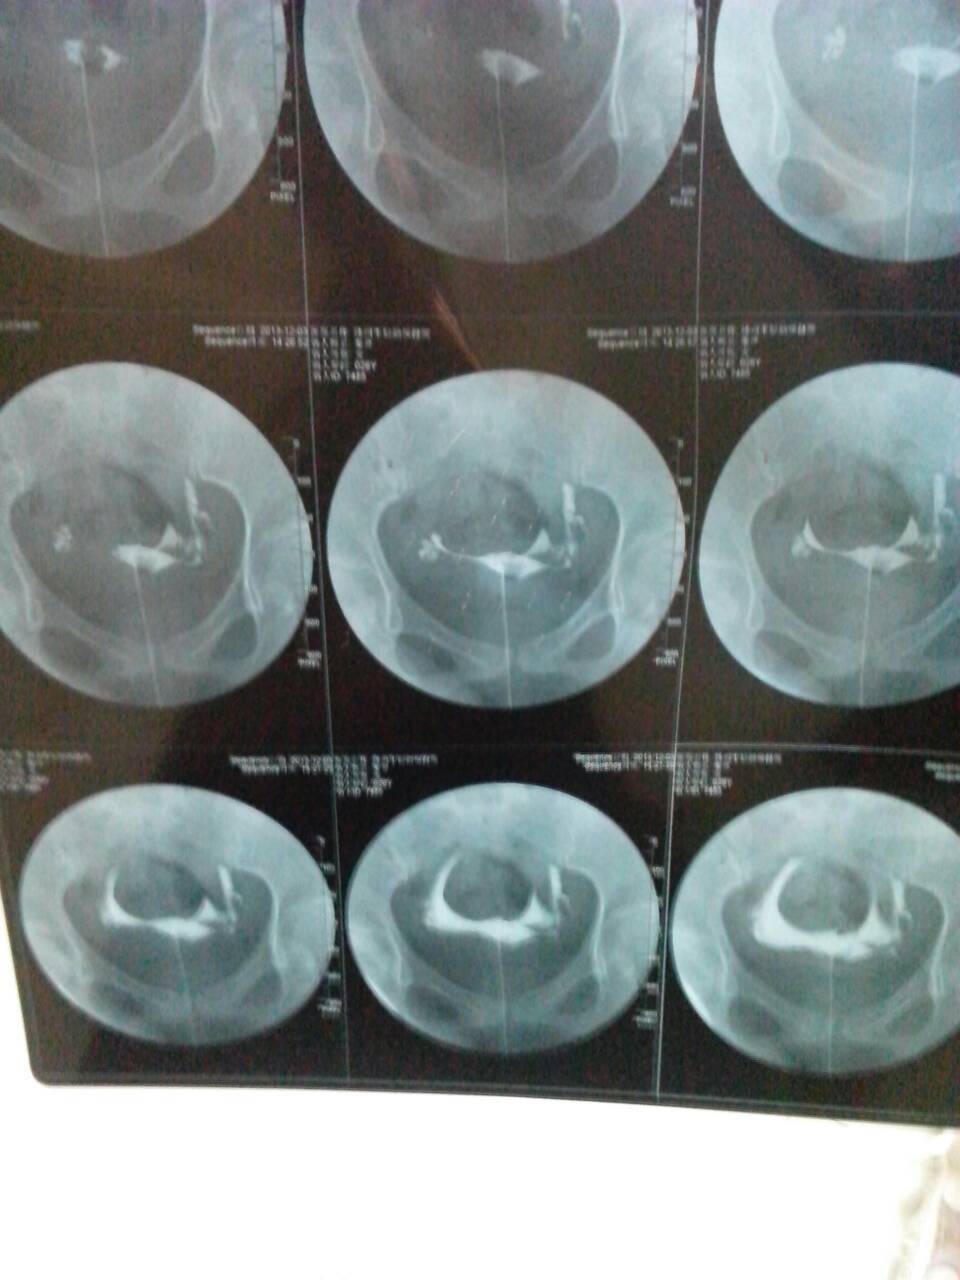

请问我这月做的输卵管造影,左侧上举,右侧不太通畅,那个大夫也不怎么负责任,片子看的不仔细,能有好心

病情分析: 您好:输卵管是精子与卵子结合的场所,输卵管阻塞是影响受孕的,但是阻塞的部位,程度,性质不同,治疗的方法也是不一样的,一般是采取微创的手术治疗的,微创手术创伤小,恢复快,受孕几率高, 指导意见: 建议您到专科医院检查,根据检查的结果,在医生的指导下对症的治疗,